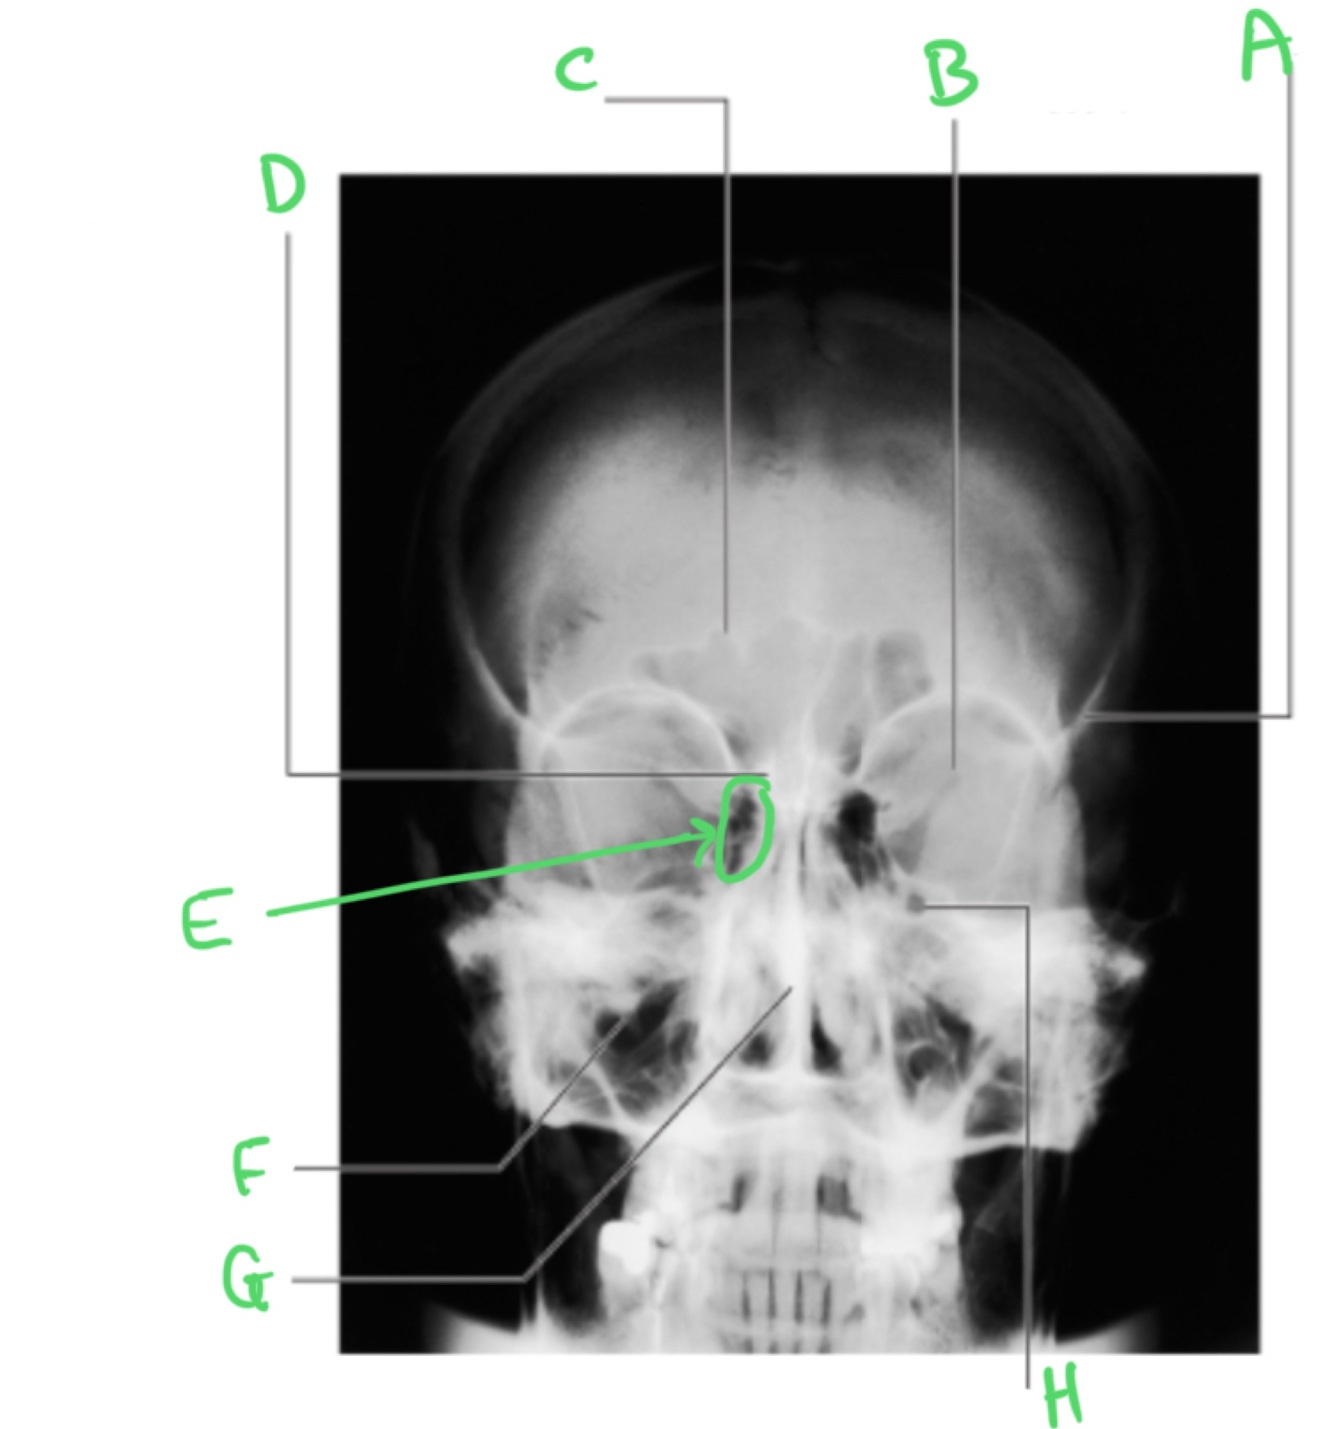

A = ethmoidal B = ethmoidal C = conchae D = middle conchae E = septum F = inferior conchae G = maxillary sinus H = uncinate process